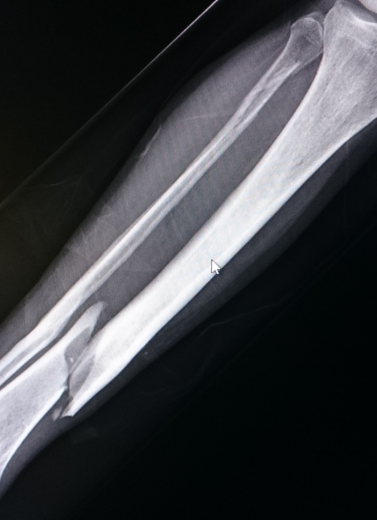

Bone fractures and trauma injuries need quick, accurate, and expert treatment to avoid long-term disability or improper healing. At our Fracture & Trauma Department, Dr. Anand Bhushan provides specialized care for all types of fractures — from simple to highly complex — using advanced surgical and minimally invasive techniques.

All surgeries are performed with infection-controlled OTs, digital X-ray support, and post-op rehab planning.

We treat each trauma case with urgency and care, beginning with imaging (X-ray/CT), followed by a personalized treatment plan. Whether surgical or conservative, our aim is quick stabilization, early mobilization, and pain control.